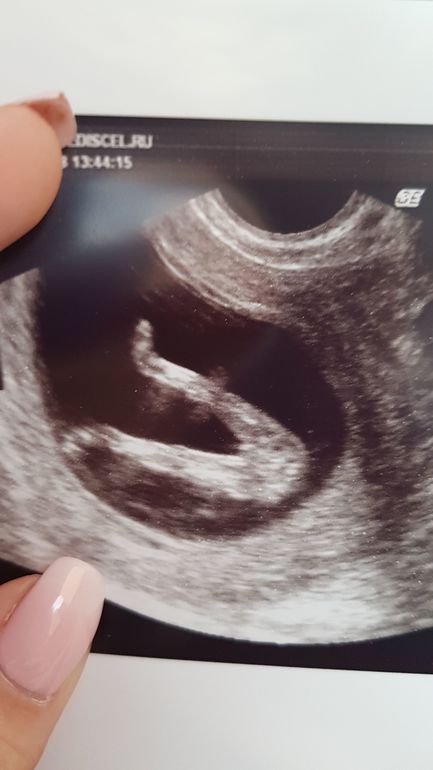

У меня правда трансвагинально делали)